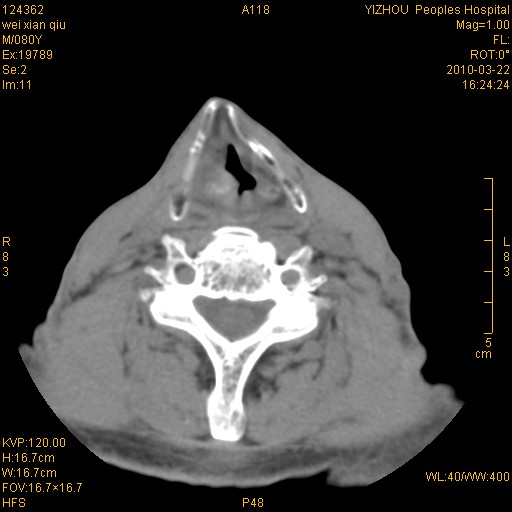

标题: CT25263:喉部占位?

男,80岁.声嘶三月余.

喉前庭右侧壁明显增厚,并见向内突出的软组织密度新生物,表面光滑,其后方软组织层次尚清晰,多考虑:喉部乳头状瘤!建议喉镜并病检!

右侧声们下区新生物

右侧声们下区新生物,建议行喉镜检查(活检)进一步明确诊断。